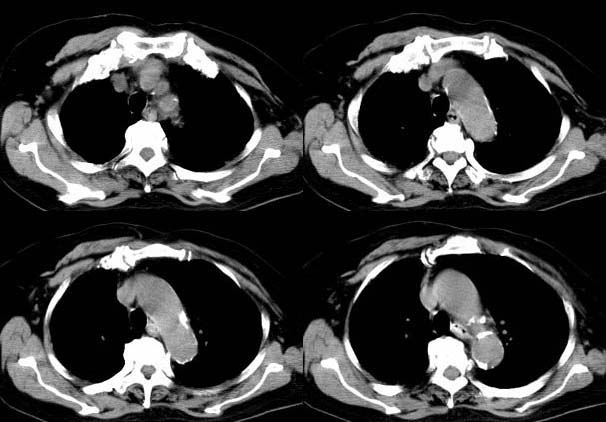

请大家讨论右下肺占位性质。ct值约35-55hu

右肺门后侧软组织肿块,内见点状钙化,年龄76,ct值约35-55hu ,考虑肺癌可能

右肺门后侧环绕支气管的软组织肿块,内见点状钙化,远端有阻塞性炎症,年龄76,ct值约35-55hu ,考虑右肺中心型肺癌。建议支气管镜鉴。

右肺中央型肺ca伴纵隔淋巴及肺内播散转移。

右下肺,右肺门后方见团块状软组织密度影,边缘呈分叶状,其内见斑点状钙化,肿块内部支气管腔闭塞。肿块后方可见胸膜尾征,外侧方见斑片状模糊阴影。右肺门淋巴结增大。

考虑:右侧中央型肺癌伴阻塞性肺炎及右肺门淋巴结转移